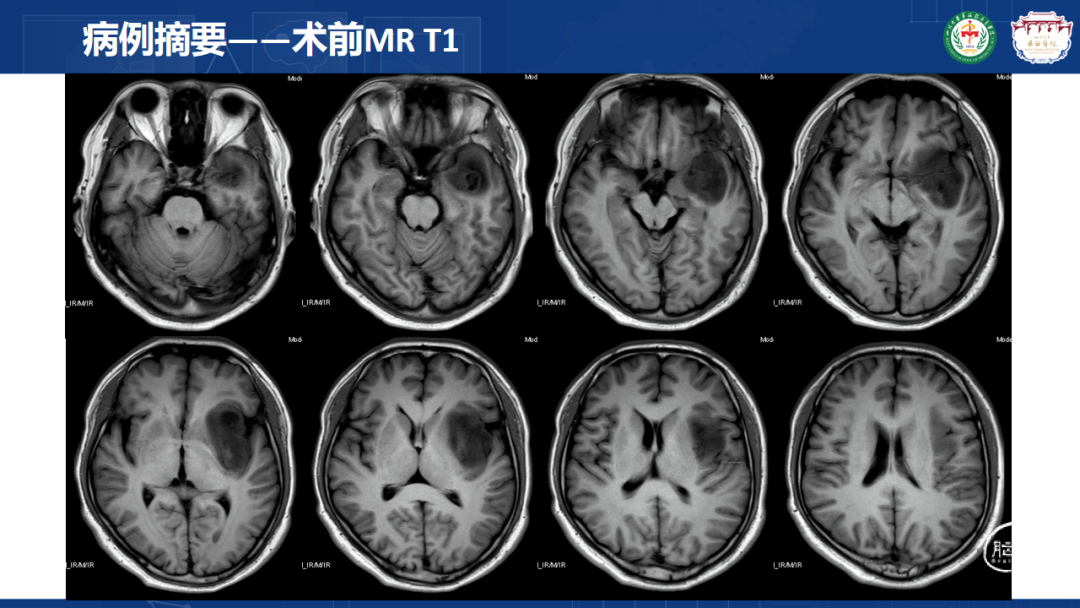

来自四川大学华西医院的曾云辉医师带来《岛叶胶质瘤手术及综合治疗》。该病例是一名41岁男性IT从业者,表现为头晕、右侧肢体麻木伴幻听,MRI显示左侧额颞岛叶占位累及海马头,DTl重建显示肿瘤包绕大脑中动脉分支。术中使用无牵拉技术联合多模态监测,经颞叶皮层造瘘切除病灶,术中重点保护侧裂静脉及M2段穿支血管。术后病理确诊为IDH突变型少突胶质细胞瘤(WHO 3级),规范实施同步放化疗联合6周期替莫唑胺辅助化疗。随访显示肿瘤控制良好,患者神经功能完整并恢复工作。